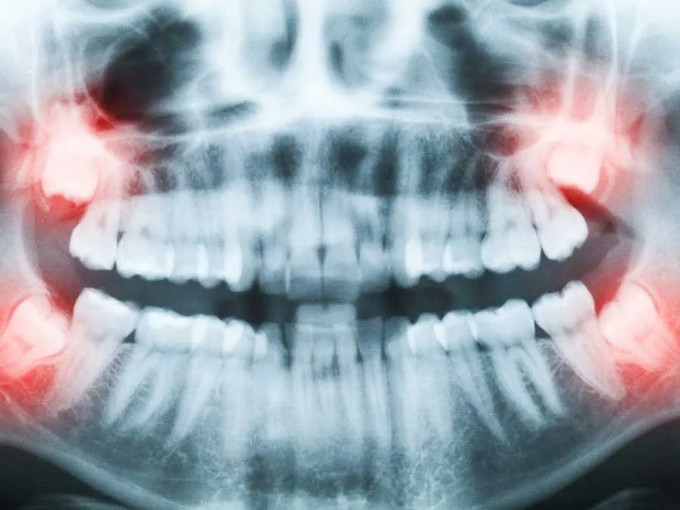

智齿通常在18~25岁萌出。因为颌骨空间不足、牙胚位置异常或角度不正,智齿长不出来,斜着或横着长,被牙龈或骨头部分或完全覆盖,就称为埋伏(阻生)智齿。这类智齿与口腔之间常形成难以清洁的“盲袋”,为细菌聚集提供条件。

4. 形成囊肿或出现占位:影像可见病灶扩大、骨质被吸收。

影像学:口腔CT(CBCT)通常是必要的,可以了解埋伏牙的位置与角度,评估根形、与下牙槽神经和上颌窦的关系。